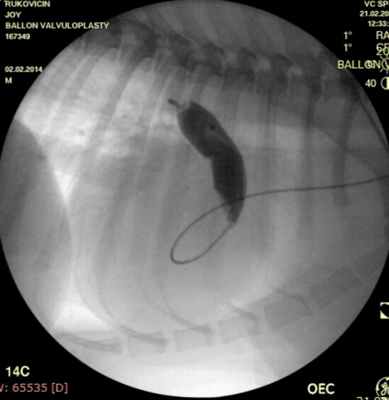

Показанием к оперативному лечению служит градиент систоличесокого давления на клапане легочной артерии свыше 50 мм рт.ст. При наличии дисплазии створок клапана — показана хирургическая коррекция порока, в остальных случаях возможно эндоваскулярное лечение. Операция выполняется в большинстве случаев под в/в анестезией, за исключением новорожденных, находящихся в критическом состоянии, у которых операция выполняется пол общим обезболиванием. Суть операции заключается в том, что после пункции бедренной вены в полость правого желудочка проводится и устанавливается катетер, далее проводник через клапан легочной артерии проводится в дистальные отделы легочной артерии. По проводнику в последующем проводится баллонный катетер и выполняется вальвулопластика. В настоящее время операция не сопровождается развитием летальных исходов и осложнений. Госпитальный период ограничен 3 днями.

Проведено: баллонная вальвулопластика клапана легочной артерии (Тип А). Баллон Cordis maxi 40х20 мм. Инфляция до 5 атм. 10 попыток.